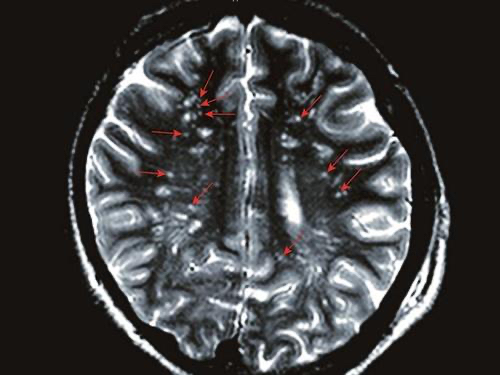

腔隙性脑梗

一、常见的腔隙性脑梗塞

腔隙性脑梗塞到底是什么?